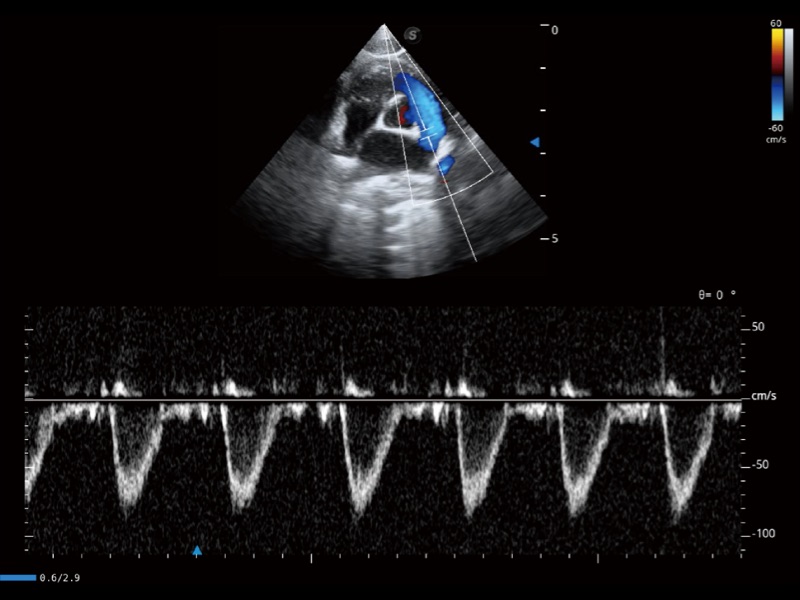

优异的基础图像

(猫)肺动脉血流频谱